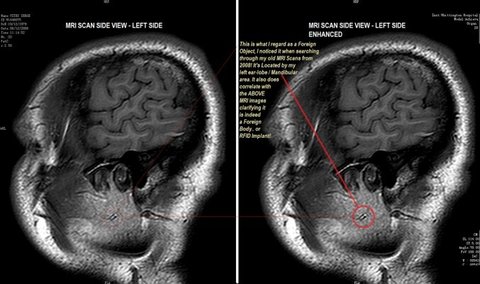

치과에서 임플란트 시술후

마인드컨트롤전파무기피해가

시작되서 임플란트를 뽑아 속을 보니 RFID칩이 발견되어 법정승소하는데 ~결정적인 증거로 작용되었다!

자신의 신체에 임플란트가 느껴지는

마인드컨트롤전파무기피해자는

TI (TargetedIndividuals)로 불립니다.